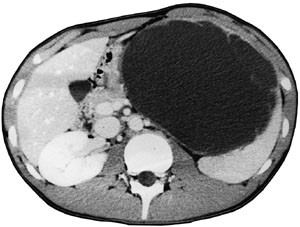

Pasient 2. 14 år gammel gutt, tidligere frisk. To måneder før diagnosen av miltcyste ble erkjent, fikk han et stumpt slag mot venstre nedre forside av brystet. Han hadde smerter i noen dager, men glemte så det hele. Seks uker senere kjente han hevelse under venstre ribbebue, og merket også litt ubehag ved fysisk anstrengelse. CT viste en cyste medialt i milten, med nærmest normal milt lateralt (fig 2). Cysten målte 16 ⋅ 13 ⋅ 13 cm. Septa ble beskrevet, men bare et lokulament. Echinokokkserologisk undersøkelse var negativ. Pasienten ble operert i 30˚ høyre sideleie. Cysten ble punktert og tømt for strågul væske. Den ble mobilisert fra venstre hemidiafragma og fra undersiden av venstre leverlapp, der den satt fast med brede adheranser. Cysten ble resecert ved deling av veggen ved overgangen til normalt miltvev. Veggtykkelsen var om lag  cm, og det var uttalt trabekulering av cystens indre vegg. Resektatet, som målte 16 ⋅ 11 cm, ble fjernet i pose via portåpningen i venstre fossa iliaca, som ble utvidet til 2 cm. Det var et ukomplisert per- og postoperativt forløp. Histologisk undersøkelse viste fibrøs miltcystevegg med stedvis plateepitelkledning (fig 3).